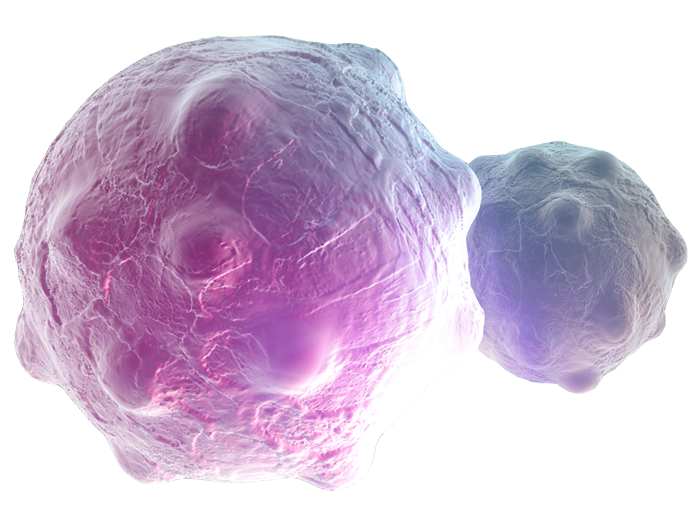

The Science of Cancer: Orchestrating a Holistic Approach to Drug Discovery

A one-size-fits all approach to cancer no longer suffices. Arriving at this understanding has been a transformative journey for the science of cancer.

The Science of Cancer: Helping More Patients Become Survivors

True dedication to making a meaningful difference to patients is what drives us. Combining our expertise and focused approach with curiosity and collaboration, is what helps us accelerate the science of cancer.